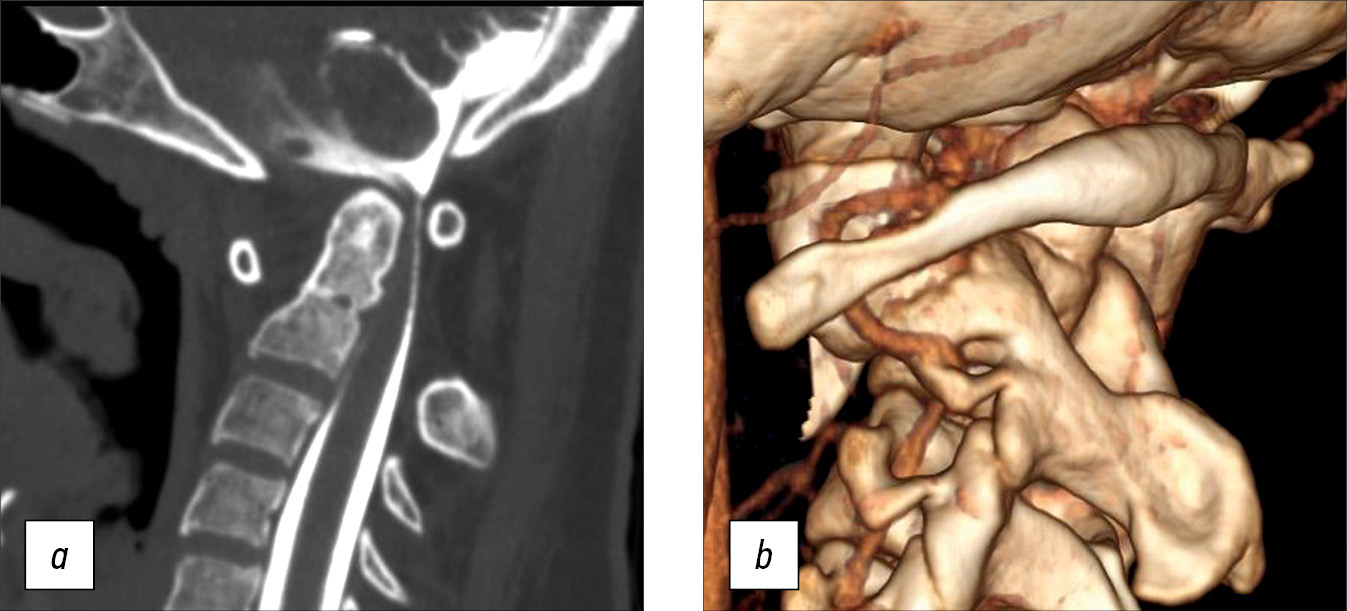

A 14-year-old female teen was admitted for a cervical spine screening examination in individuals with Down syndrome. She complained of progressive weakness in the upper and lower extremities and forced head position with rotation to the right for the past 3 months. Results of the CT and MRI of the cervical spine led to the following diagnosis: Down syndrome, rotational atlantoaxial blockage, left-sided chronic transligamentous subluxation of the C1 vertebra with spinal canal stenosis (Fielding–Hawkins type II), cervical myelopathy, and deep tetraparesis (Frankel C) (Fig. 2).

Fig. 2. Instrumental methods of examination: a — MRI picture of transligamentous subluxation with spinal canal stenosis and myelopathy at the level of C1-C2, b — 3D CT reconstruction, c — CT scan of the cervical spine, sagittal slice with visualization of disturbed craniovertebral relations. MRI — magnetic resonance imaging, CT — computed tomography.

CT revealed gross violations of craniovertebral relationships: the Cruveilhier joint gap (atlantodental interval [ADI]) was 1.06 cm, and the space available for the spinal cord at the C1 level (SAC C1) was 5.17 mm. These changes indicate gross stenosis of the spinal canal. A bone block developed in the left lateral atlantoaxial joint (Fig. 3)